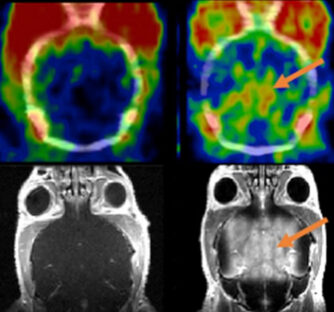

Thérapie par ultrasons focalisés pour accroître le passage de la BHE